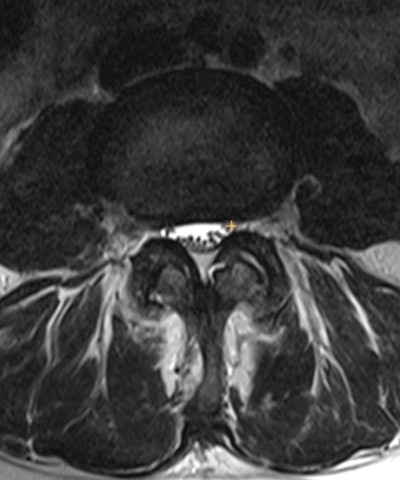

Inclusion criteria consisted of MRI lumbar spine studies with a sagittal "T2-like" (e.g., conventional spin echo T2, STIR, or Dixon), sagittal T1, and axial T2 weighted images. Volunteer annotators graded the degree of stenosis using a four-point scale of normal, mild, moderate, or severe for the following locations: spinal canal (labeled on the T2-like sequence), right and left neural foraminal (sagittal T1), and right and left subarticular recess (axial T2).

(A, B) MR images (A, sagittal T2; B, sagittal STIR) demonstrate the location of the localizers within the middle of the thecal sac at the level of the L1/L2 through L5/S1. Images and caption courtesy of the RSNA.